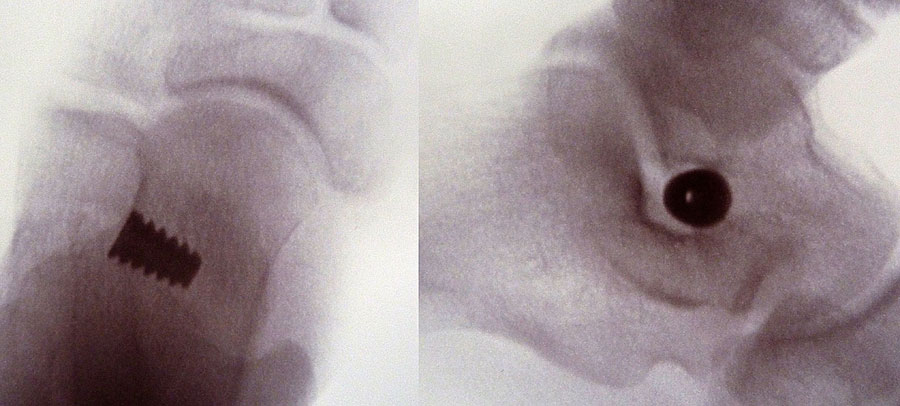

• Sehr sicheres Verfahren sobald der Führungsdraht im Sinus tarsi platziert ist. Das zugehörige Instrumentarium, alle Probeimplatate und auch das endgültige Implantat sind kanüliert und werden stets über diesen Guidepin geführt.

• Fehlplatzierungsrisiko durch Führungsdraht und Durchleuchtungskontrolle gering.

Röntgenkontrolle d.p. und seitlich unter Belastung nach 2, 6 und 12 Wochen und Beurteilung des Ergebnisses im Vergleich mit den präoperativen Bildern.

• Röntgenkontrolle d.p. und seitlich unter Belastung nach 2, 6 und 12 Wochen und Beurteilung des Ergebnisses im Vergleich mit den präoperativen Bildern (Abb.15).